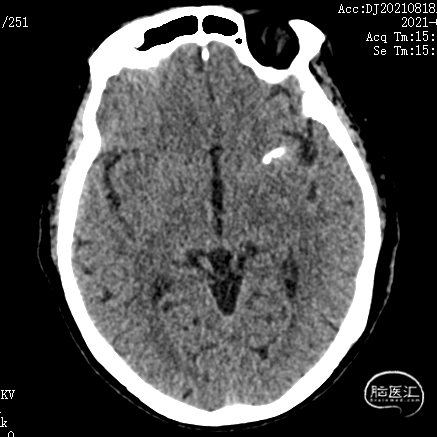

术后3天复查CT示:

1. 双侧基底节区腔隙性脑梗死;

2. 老年性脑改变;

3. 左侧颞叶致密影,考虑术后,请结合临床病史。未见大脑前载瘤动脉远端存在缺血。

术后6个月复查造影示:弹簧圈致密充填瘤体内,瘤体消失,左侧颈内动脉及大脑前、中动脉均显影良好,载瘤动脉通畅,形态和血管直径较动脉瘤栓塞前无明确变化。支架形态良好,未见移位及血栓形成。